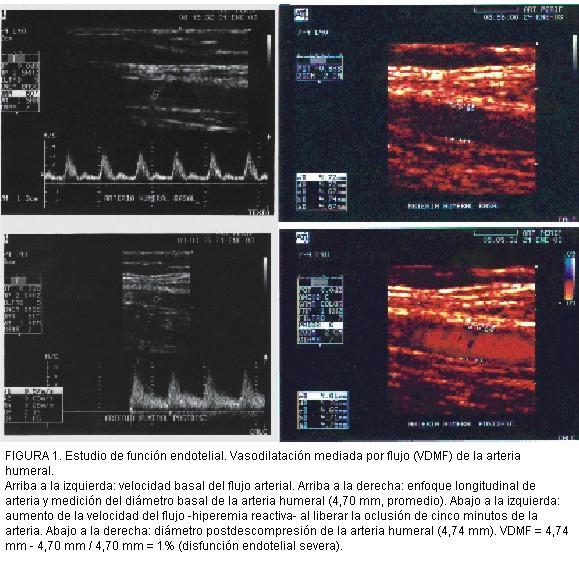

FIGURA 1. Estudio de función endotelial. Vasodilatación mediada por flujo (VDMF) de la arteria humeral.

Arriba a la izquierda: velocidad basal del flujo arterial. Arriba a la derecha: enfoque longitudinal de arteria y medición del diámetro basal de la arteria humeral (4,70 mm, promedio). Abajo a la izquierda: aumento de la velocidad del flujo -hiperemia reactiva- al liberar la oclusión de cinco minutos de la arteria. Abajo a la derecha: diámetro postdescompresión de la arteria humeral (4,74 mm). VDMF = 4,74 mm - 4,70 mm / 4,70 mm = 1% (disfunción endotelial severa).